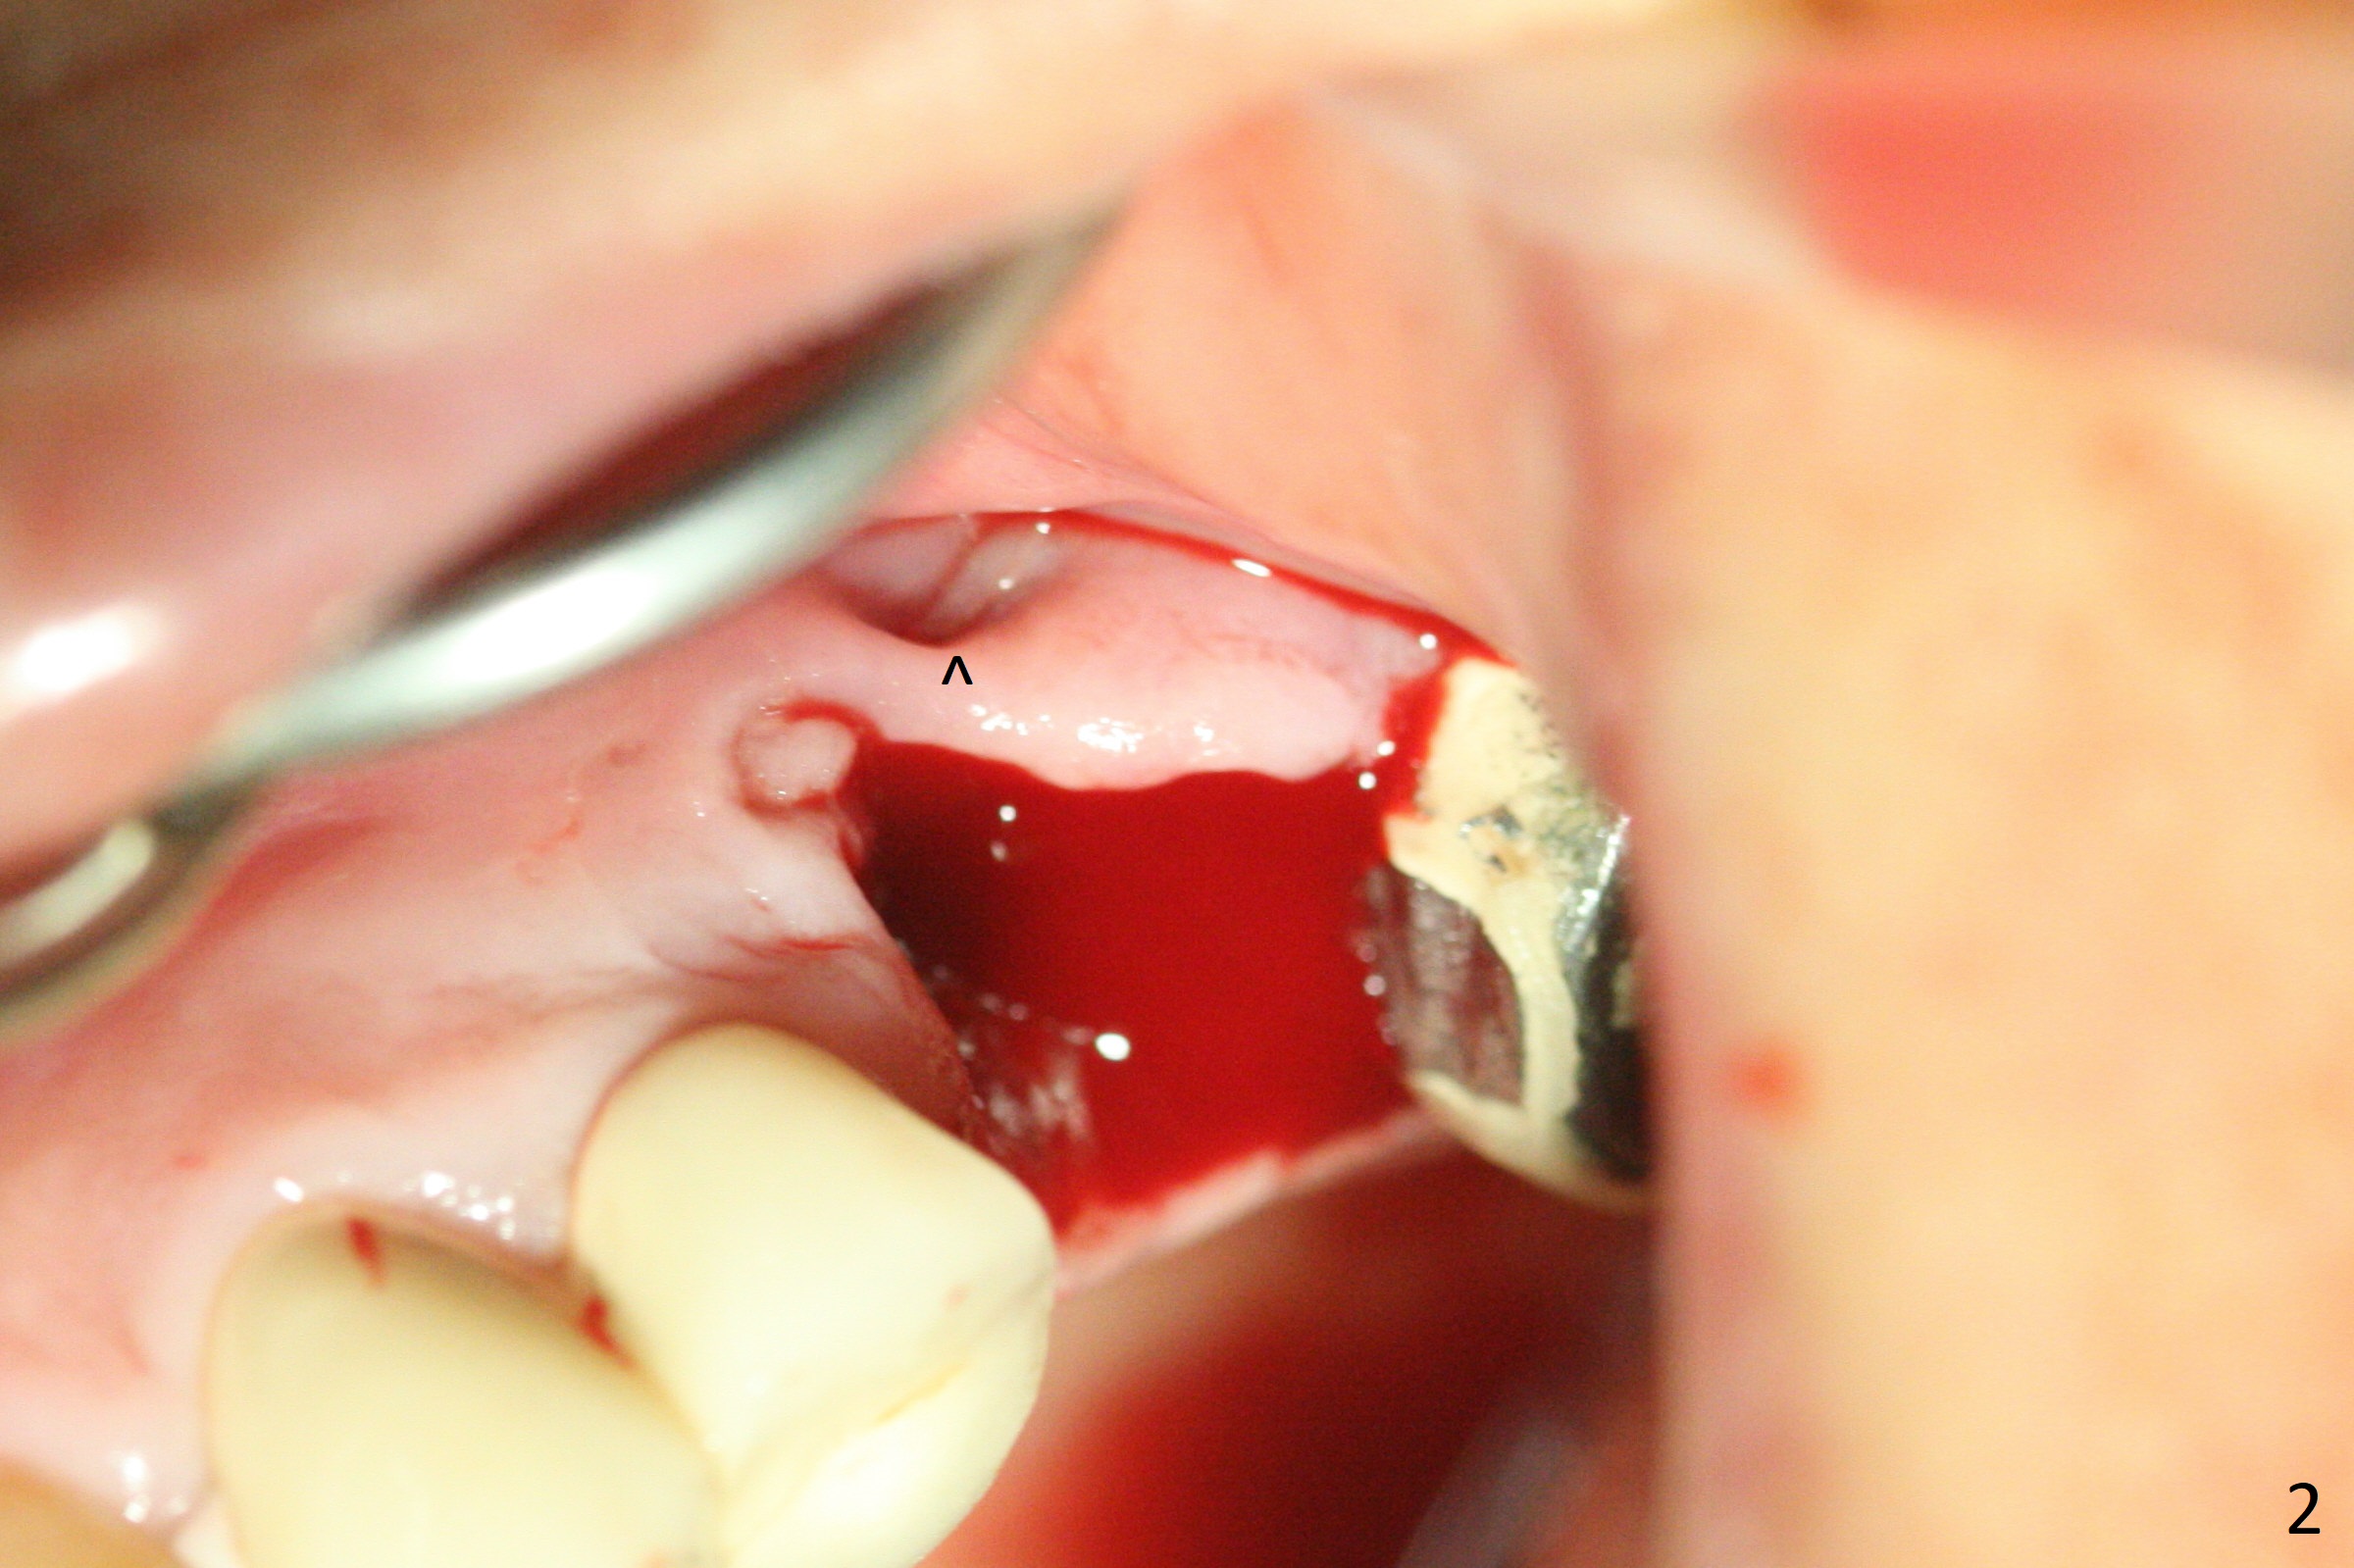

A 49-year-old woman returns for removal of the tooth #14 with loss of the buccal plate (Fig.1 red dashed line). After extraction, the buccal gingiva collapses as a dimple (Fig.2 ^). Cytoplast, a Titanium-Reinforced Non-resorbable Membrane (Fig.3), is used after bending (Fig.4) to assist in repair of the buccal plate with bone graft (Fig.5,6). As compared to Fig.1, the bone height also increases. Periodontal dressing and Cytoplast dislodge with odor 10 days postop (Fig.7,8). Periodontal dressing is re-applied. Spacer or acrylic dressing should have been used for security. In spite of the narrow ridge 5 months postop (Fig.9), a 5x11.5 mm bone level or 5x17 mm tissue-level implant is possible (Fig.10). But the implant should be placed more palatal, away from the buccal defect!